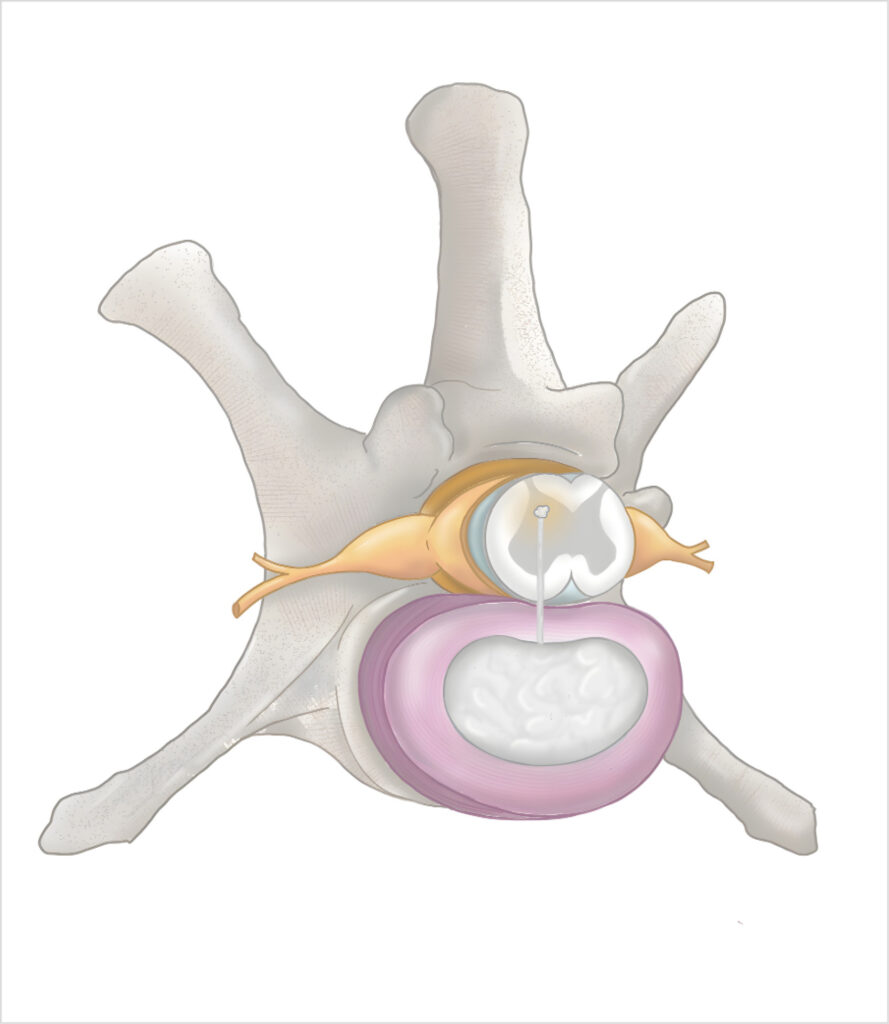

Estas últimas suelen ocurrir de forma aguda o hiperaguda, no son progresivas, pueden cursar con o sin dolor evidente y en cualquier raza y edad. En la anamnesis es importante preguntar a los tutores si, previamente a la presentación, el paciente ha estado haciendo ejercicio, jugando o ha sufrido algún traumatismo, ya que se dan a partir de movimientos bruscos de la columna vertebral que provocan una ruptura del anillo fibroso, penetración en la dura y en la médula espinal, donde pueden causar gliosis, edema y hemorragia (imagen 1- ver).